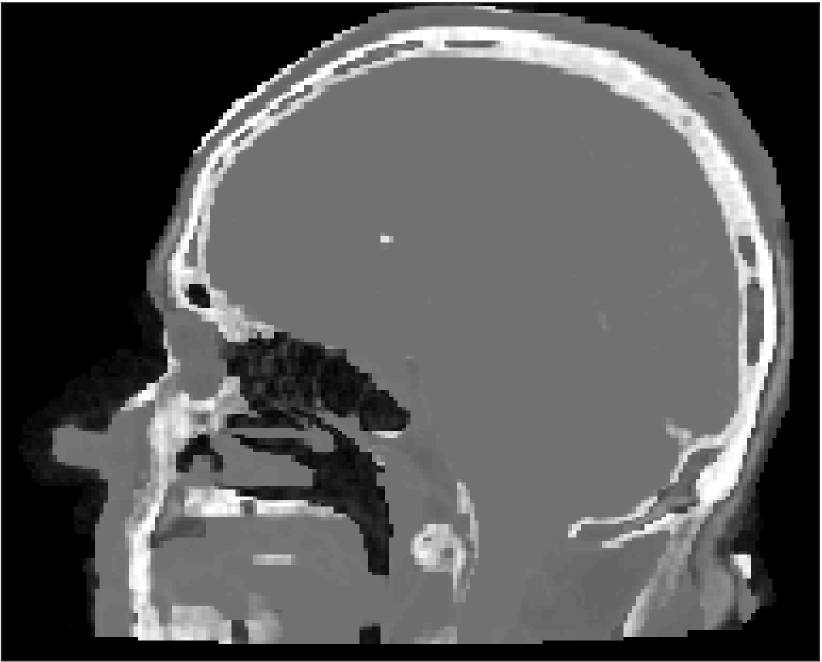

All MR images were acquired with a 1.5 T Siemens Espree scanner. The UTE images were reconstructed to 192×192×192192192192192\times 192\times 192 voxel bitmapped images with an isotropic resolution and a voxel size of 1.33 mm. The UTE sequences sampled the k-space radially with 30 000 radial spokes. CT images were acquired with a tube voltage of between 120 kV and 130 kV on either a GE Lightspeed Plus, Siemens Emotion 6 or GE Discovery 690. The in-plane pixel size varied between 0.48 mm to 1.36 mm and the slice thickness between 2.5 mm and 3.75 mm. Images of the same patient were co-registered and resampled to achieve voxel-wise correspondence between all five modes. A binary mask excluding most of the air surrounding the head was computed from the images and used to remove unnecessary data. Furthermore, to reduce the execution time of the parameter estimation phase, only 11 slices in the middle of the head of each patient was used during the parameter estimation phase, but all slices were used during the prediction phase (s-CT generation). Additional details concerning the data can be found in Johansson et al. [16]. Data from one slice of a patient is shown in Figure 3.

Refer to caption

(a) Binary mask

(b) CT

(c) First echo, 10superscript1010^{\circ}

(d) Second echo, 10superscript1010^{\circ}

(e) First echo, 30superscript3030^{\circ}

(f) Second echo, 30superscript3030^{\circ}

Figure 3: Binary data mask (panel a), CT image (panel b), The four MRI UTE sequences (panels c-f).